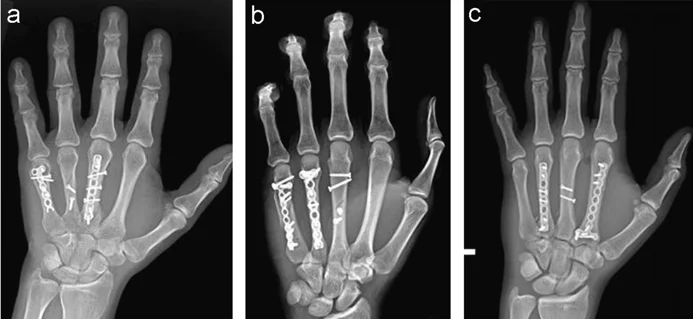

Metacarpal Fractures

- Careful about rotational malalignment

- Check rotation by flexing the fingers

Finger malrotation

- Undisplaced / or only one MC

- Treatment by cast / or splint

- Displaced / Rotated / Multiple

- Treated by internal fixation (screws / plates / wires)